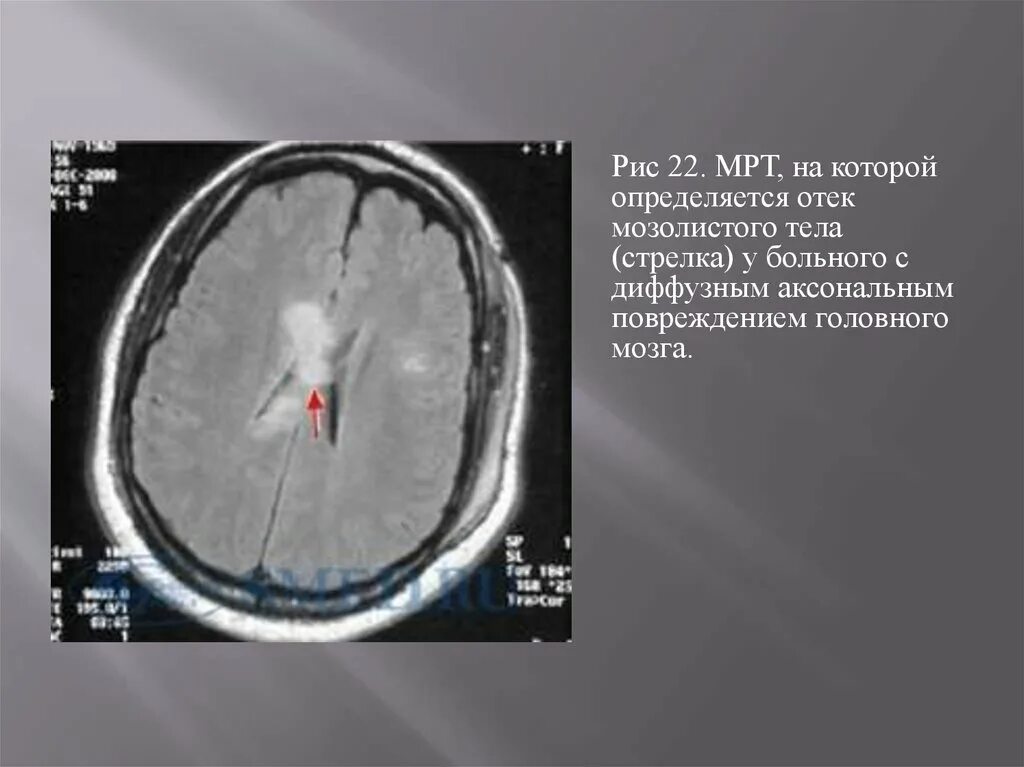

Диффузные повреждения